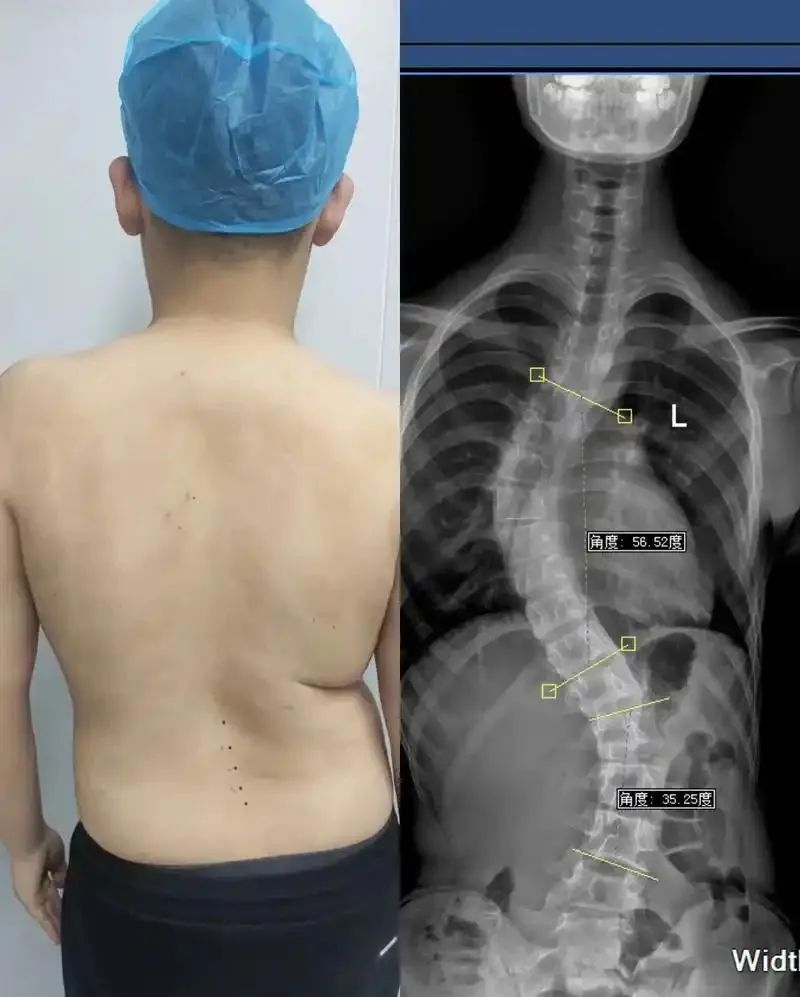

近些年,脊柱问题越来越严重,甚至越来越年轻化!

脊柱侧弯、脊柱炎、颈椎病、腰椎间盘突出...

这些病单看名字其实还好,很多都是“常见病”,但这些病一旦得了一种,时间久了对我们的身体都是“毁灭性”的打击!

现如今,有脊柱问题的人越来越多,脊柱病也越来越年轻化,而究其病因,很多都适合我们不良的生活习惯有关!

二郎腿、“葛优瘫”、躺着看手机、久坐、缺少运动...